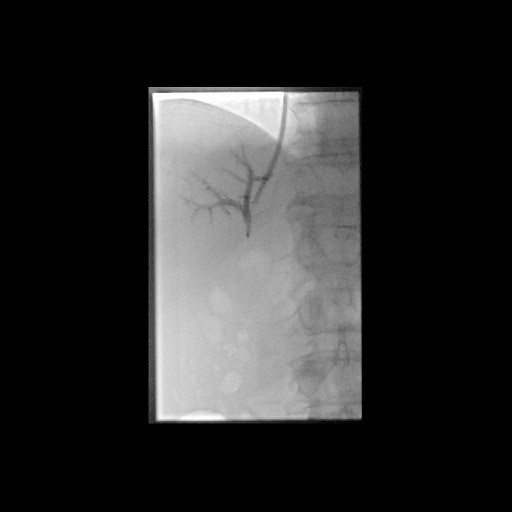

« Zurück Erfolgreiche Implantation eines transjugulären intrahepatischen portosystemischen Shunts (TIPSS) bei Leberzirrhose und refraktärem Aszites. Darstellung der Lebervenen (Bild 2 von 4) Vorwärts »

« Zurück Erfolgreiche Implantation eines transjugulären intrahepatischen portosystemischen Shunts (TIPSS) bei Leberzirrhose und refraktärem Aszites. Transhepatische Punktion der Pfortader unter sonographischer Kontrolle (Bild 3 von 4) Vorwärts »